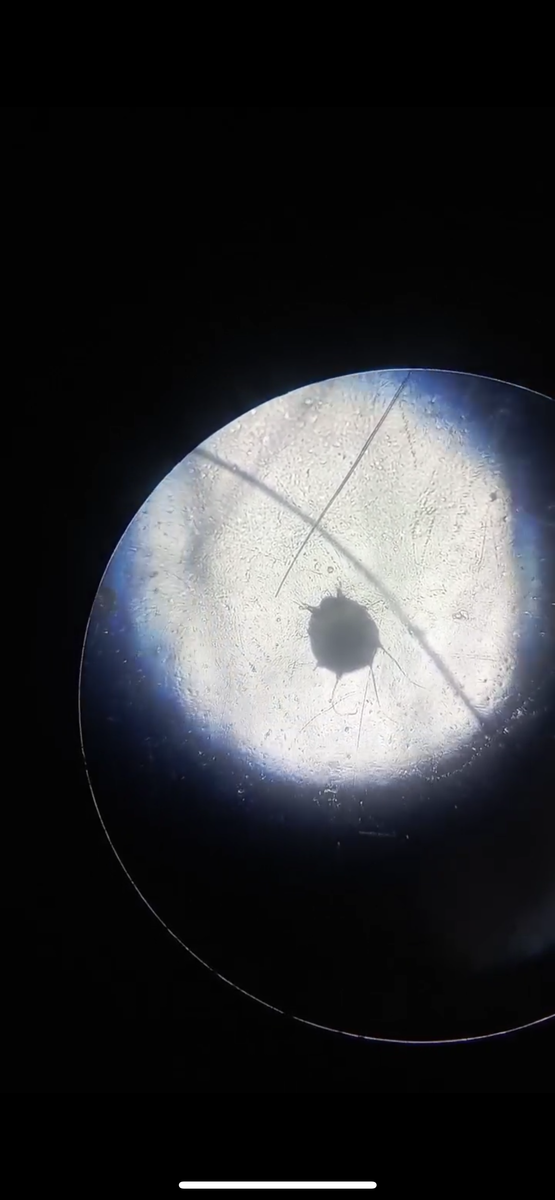

Фото взято из интернета

Для подтверждения диагноза ветеринар проводит:

1. Соскоб кожи с последующей микроскопией (обнаружение клещей, яиц или их фекалий).